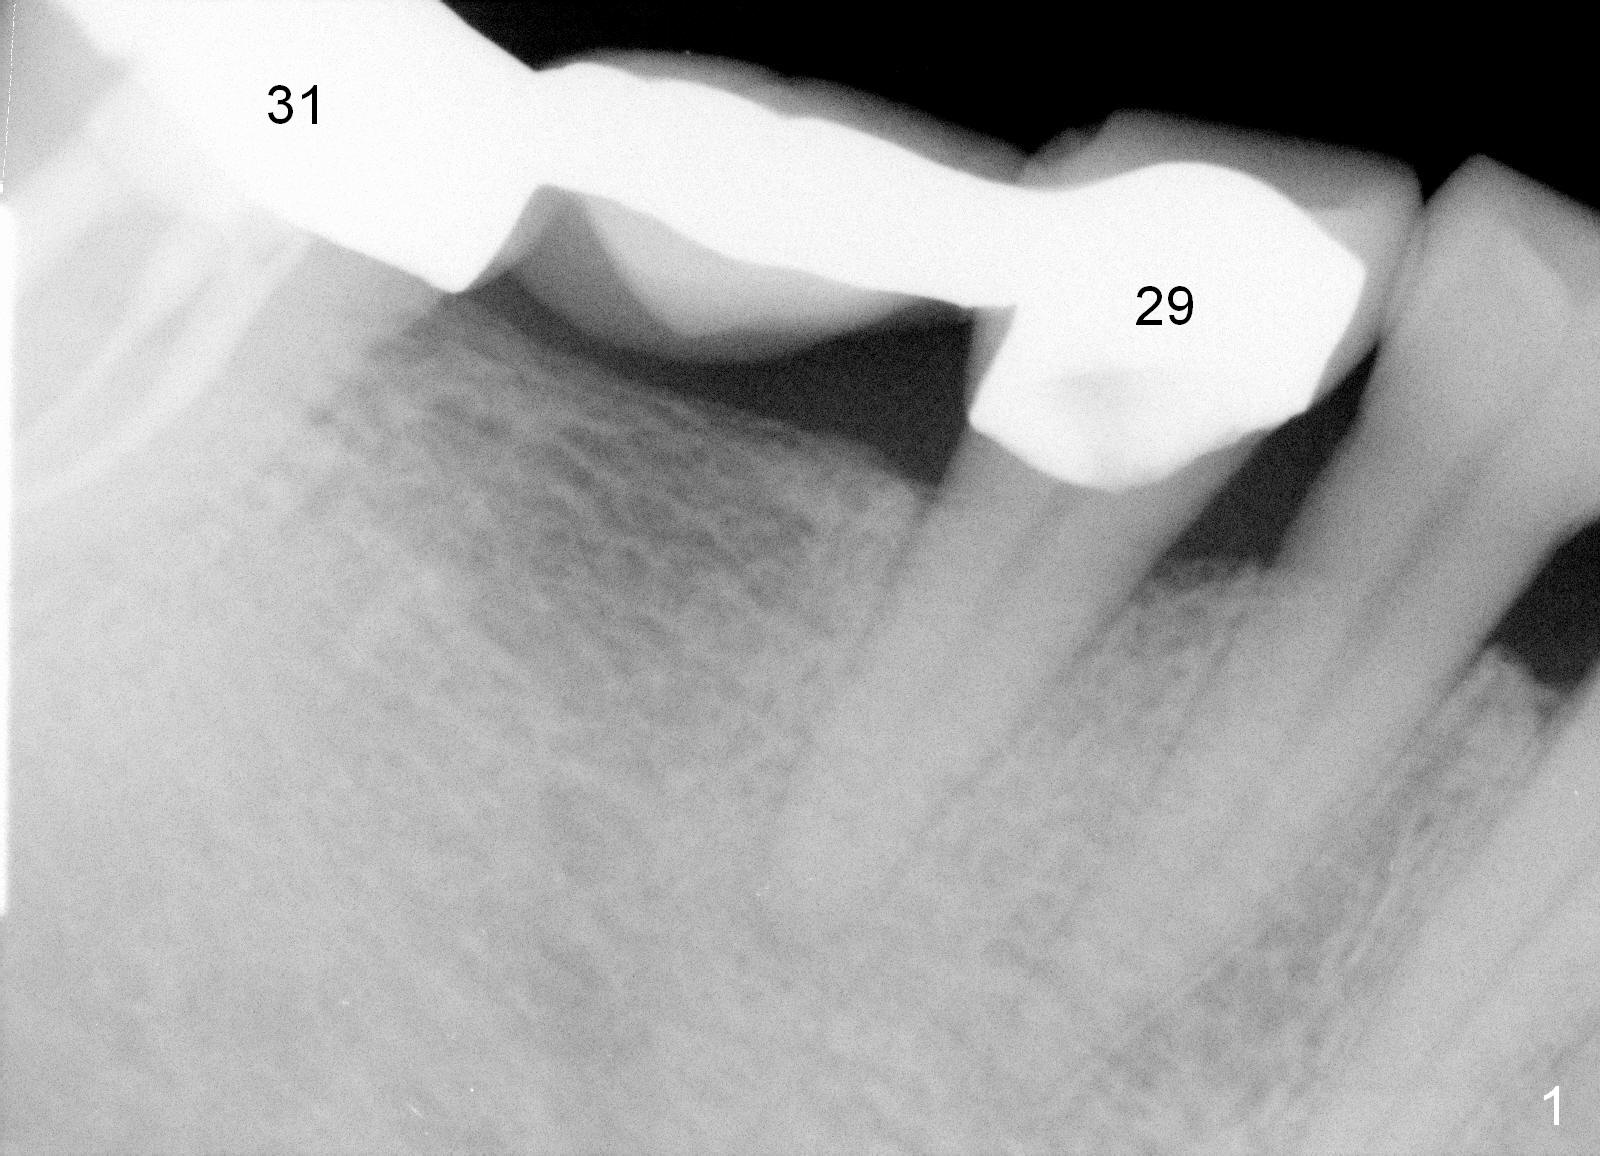

A 47-year-old man has history of bruxism, chipping porcelain from #29-31 FPD (Fig.1). Following sectioning the FPD, osteotomy is created (Fig.2: 5x14 mm drill) for placement of a 5x14 mm tissue-level implant (Fig.3,4). A 4x3 mm abutment (Fig.5 (lingual view) A) with 3 vertical slots (* for increased retention) is placed to retain periodontal dressing. The crown over the implant has dislodged 3 times over 28 months post cementation (Fig.6). It appears that the top of the abutment is too rounded. Clinical exam shows that the abutment height can be more, although the tooth #3 is supraerupted (Fig.7 (orthodontic intrusion is not indicated because of furca infection)).